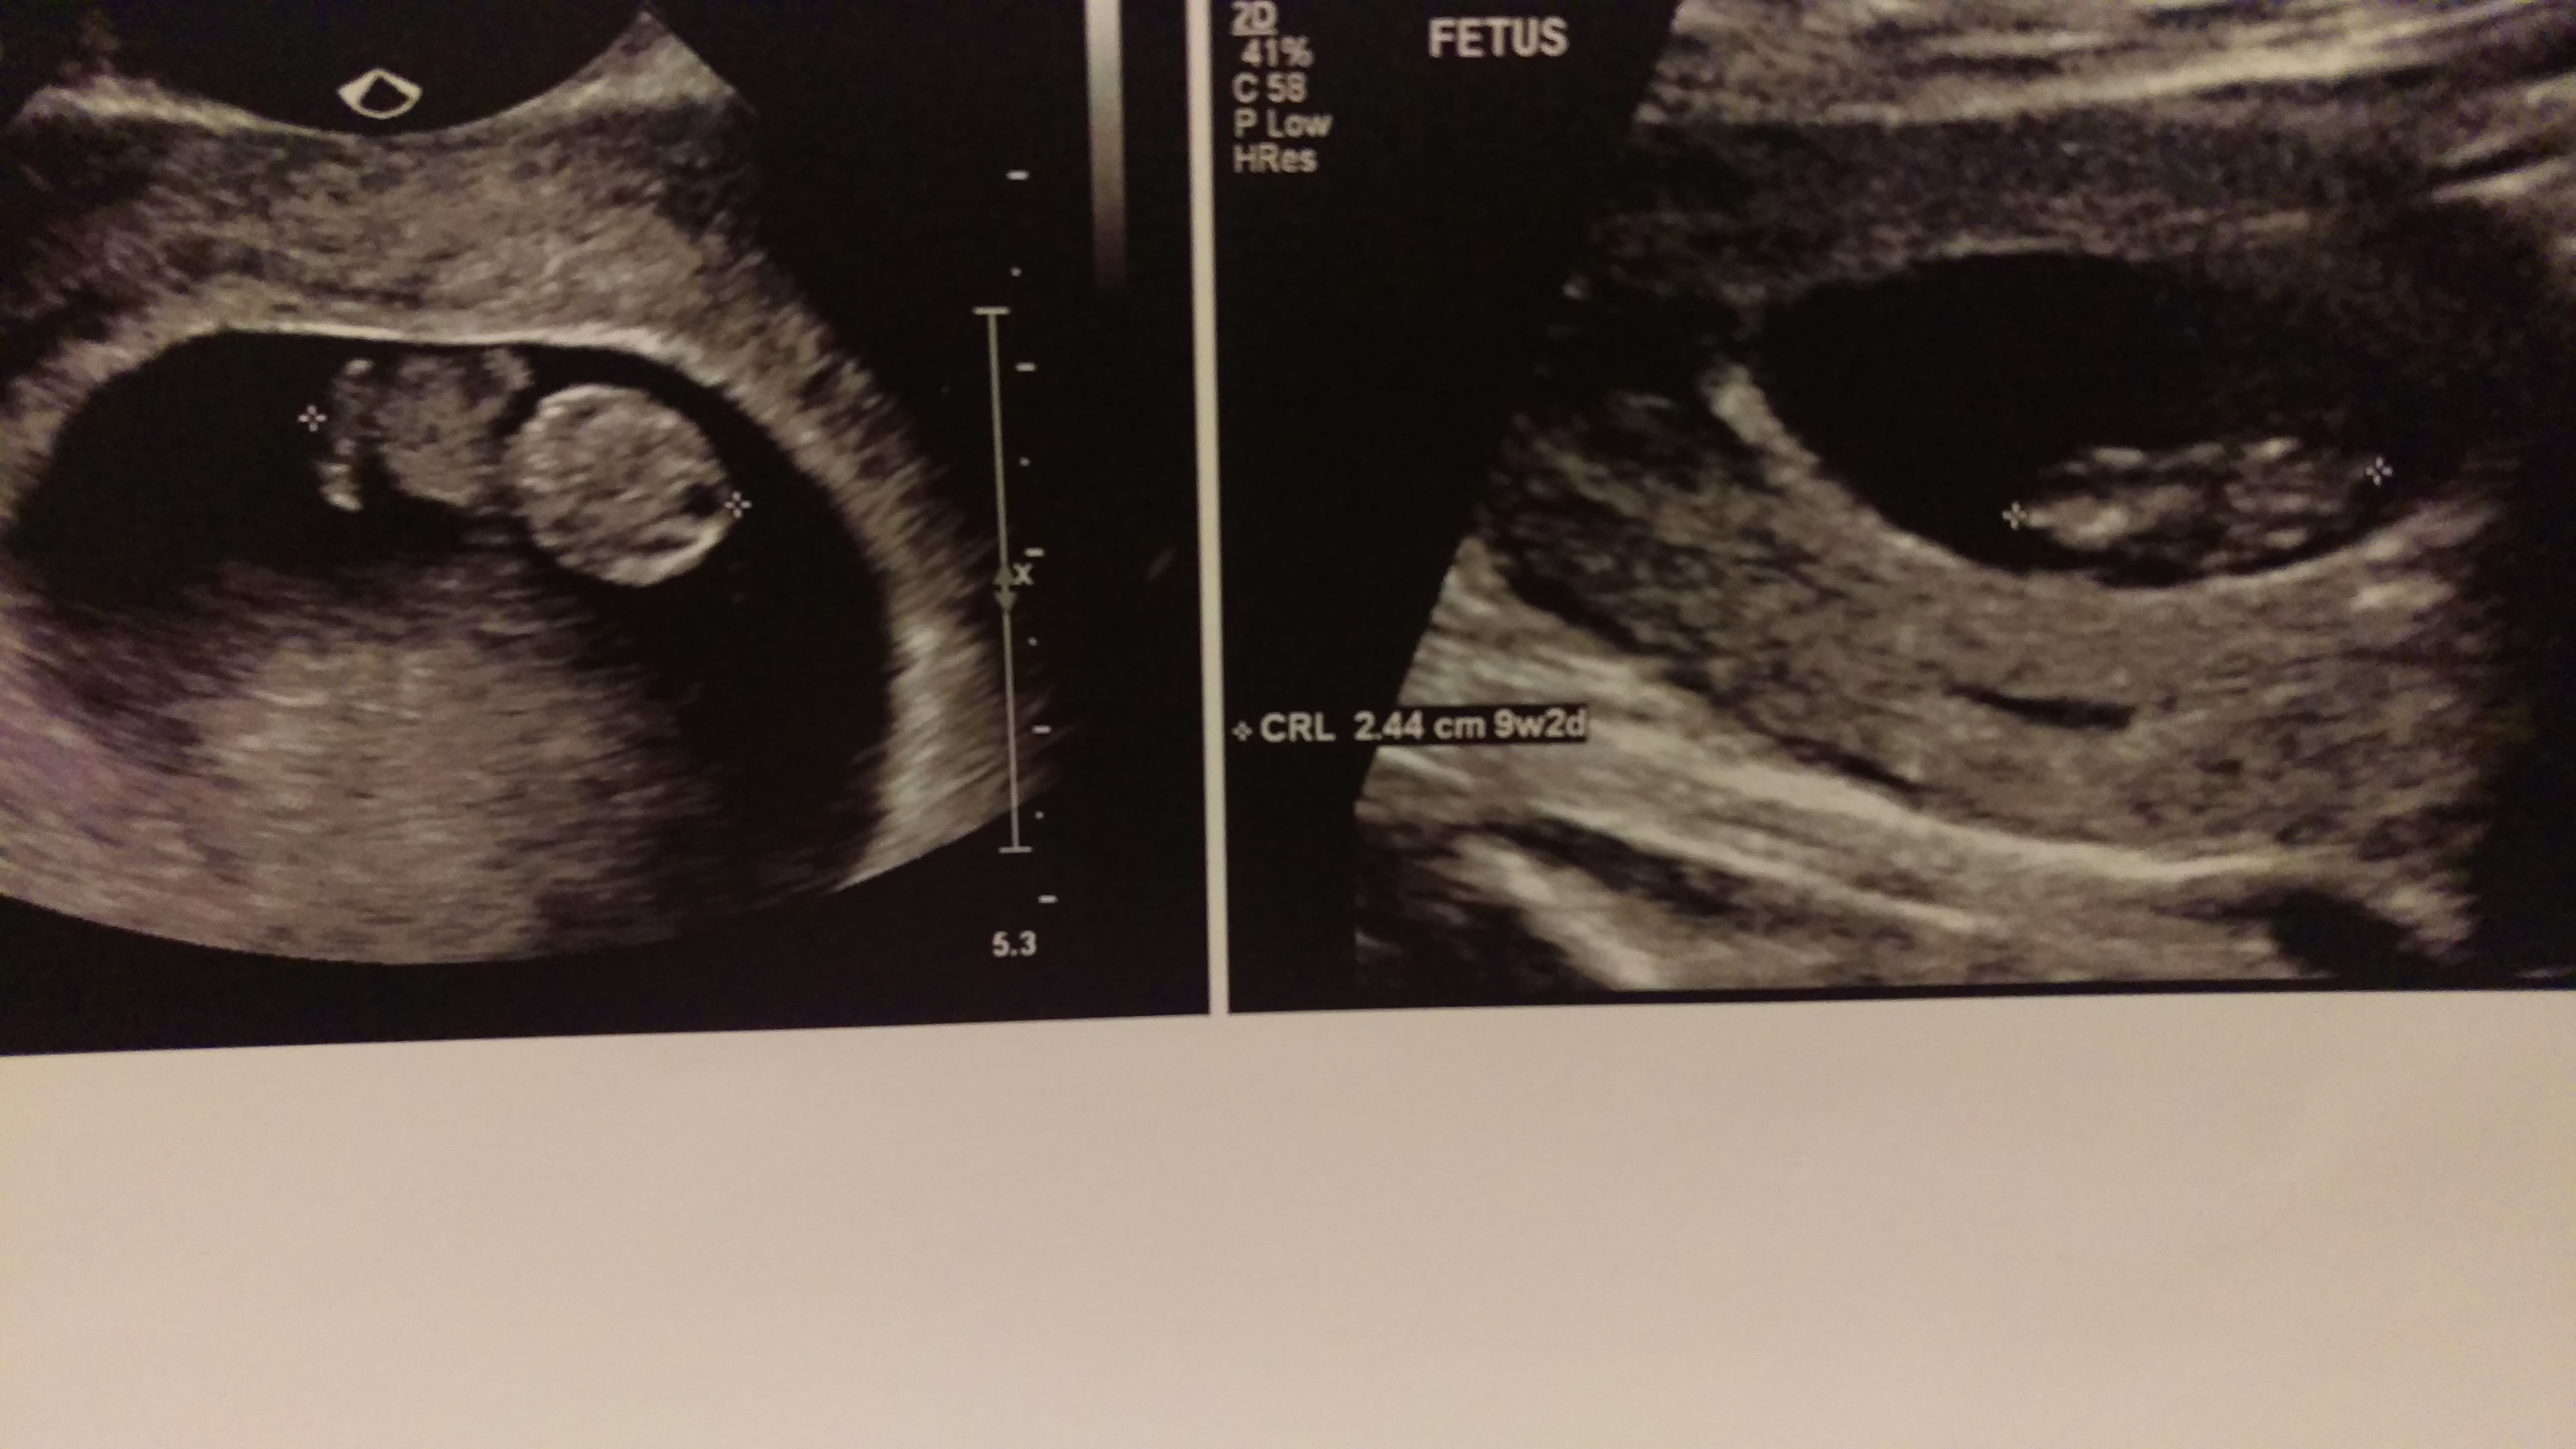

8 week ultrasound and there's twins! We were only able to see one heart beat and they thought I'm a week behind where I thought I was so please send good growing thoughts my way. Headed back in a week to hear Baby B. also if anyone has had experience in this area, please advise.</p>

Headed in this am to have second ultrasound. I need all the strength and good energy that's possible now. Definitely very nervous.

One strong and growing baby. We are grateful for that❤️